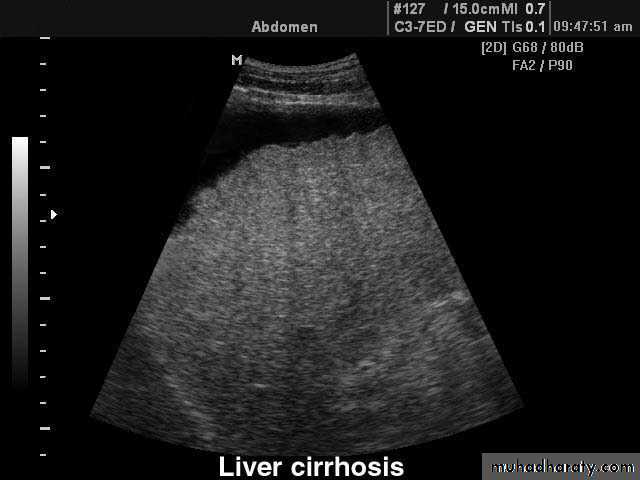

Cirrhosis & portal hypertension